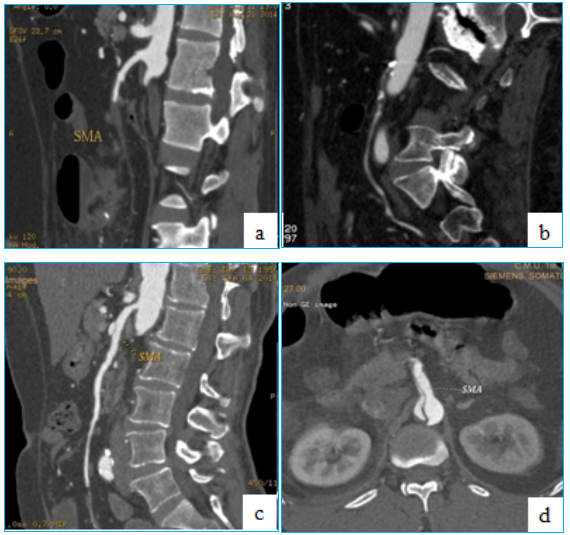

71岁男性,腹痛2天,房颤患者。

通过开腹取栓+肠切除

术后恢复良好

★ 案例二

68岁,男性,突发剧烈腹痛10小时,陈旧性心肌梗死、心房颤动,曾在外院按照急性胆囊炎诊治,因腹痛明显加重来我院急诊。行开腹探查+肠系膜上动脉取栓术。

CTA示SMA栓塞。在Straub导管吸栓后,利用腹腔镜确认肠管活力,避免了不必要的大切口。这展示了腔内与微创技术结合的可能性。